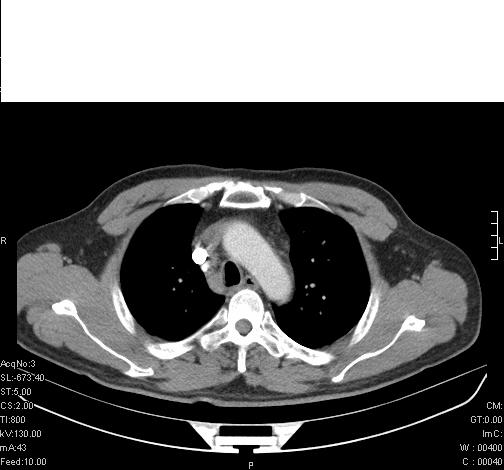

前几天,发了患者的平扫片,患者抗炎一周后增强扫描。右中叶病灶吸收明显,但下叶病灶未见明显吸收。右肺门可见结节影,看来凶多吉少

右肺下叶支气管壁明显增厚,考虑癌症并阻塞性炎症、肺门淋巴结肿大

考虑右肺癌并阻塞性炎症、肺门淋巴结肿大

还是考虑右肺中央型肺癌可能性大

考虑右肺中央型肺癌可能性大

右主支气管狭窄,管壁增厚。考虑右中心性肺ca伴阻塞性肺炎。